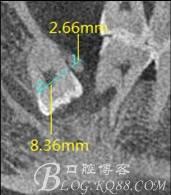

圖6.測量48頰、舌側骨板厚度。

圖7.測量牙冠近遠中徑的大小及遠中骨板的厚度